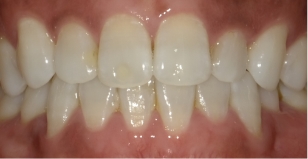

しかし当院の歯並びもよく観察すると、少しは指数が増加、つまり多少は歯並びが悪くなっていることが分かります。実はこれは自然な歯並びの変化と同じものである事がわかりました。つまり歯並びは下の写真が示すように矯正をしてない人でも、変化するのです。その自然な変化をリトル教授のお仲間のシンクレア先生が報告しており、そのデータを追加したのが下の図です(グラフのグレー)。これをみると元々綺麗な歯並びだったものも7年経過するとリトルの指数が35%も増加していることが分かります。

当院のリトルの指数の増加は5年で31.9%でしたが、今回の調査で、伊藤矯正歯科医院の治療後の変化は自然な変化と「統計的に差はない」という結果が出ました。

自然な歯の移動